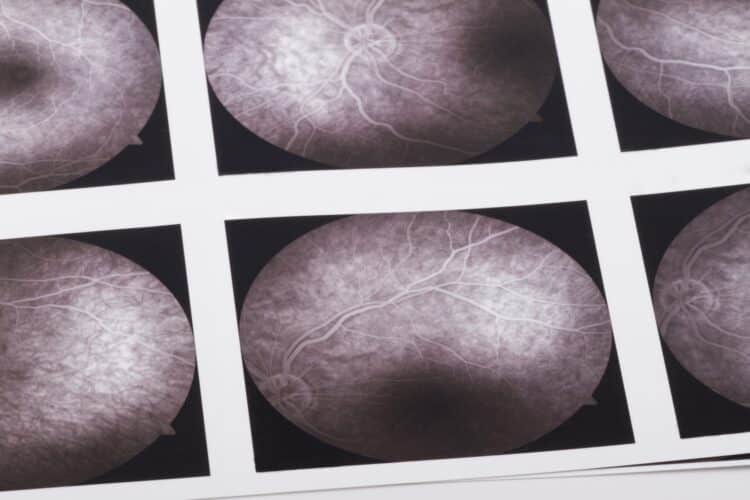

W odpowiedzi na te wyzwania, naukowcy opracowali model „Eye-AD”, który analizuje dane z obrazów OCTA (ang. Optical Coherence Tomography Angiography) — nowoczesnej techniki obrazowania siatkówki. OCTA dostarcza szczegółowych informacji o mikrostrukturach naczyń krwionośnych w siatkówce, pozwalając na badanie nawet najmniejszych naczyń o rozdzielczości 5–6 μm. Dzięki temu można uzyskać szczegółowy wgląd w zmiany mikrokrążenia siatkówki, które mogą być powiązane z procesami neurodegeneracyjnymi, takimi jak te związane z chorobą Alzheimera.

Badanie obejmowało analizę danych z dwóch głównych grup: ROMCI (Retinal OCTA-based MCI detection) i ROAD (Retinal OCTA-based EOAD detection), które dostarczyły obrazów siatkówki niezbędnych do trenowania i oceny modelu.